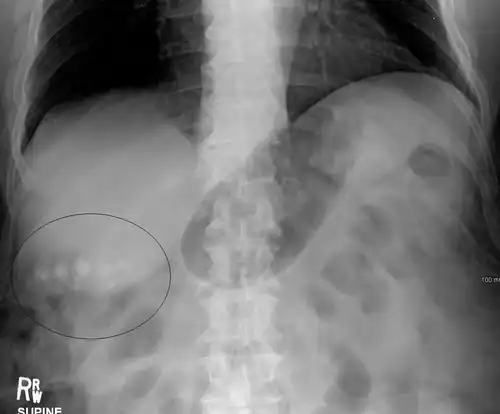

Gallstones as seen on plain X-ray

Gallstone ileus

Large gallstones can potentially erode through the gallbladder wall and into the neighboring small intestine. This large stone then travels through the small intestine until it is too narrow for the stone to continue, causing a small bowel obstruction. This obstruction often occurs at previous surgical sites or at the ileocecal valve (the portion of the bowel where the small intestine meets the large intestine). The patient presents with the inability to defecate or pass gas, nausea, vomiting, and severe abdominal pain.[14]